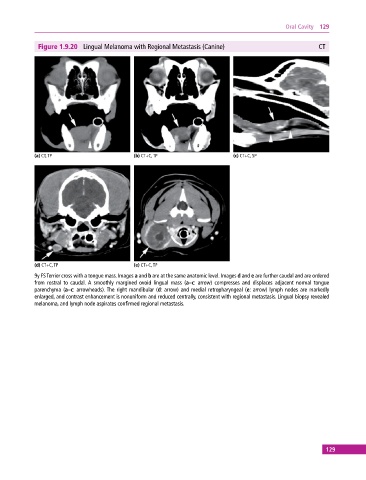

Figure 1.9.20 Lingual Melanoma with Regional Metastasis (Canine) CT

(a) CT, TP (b) CT+C, TP (c) CT+C, SP

(d) CT+C, TP (e) CT+C, TP

9y FS Terrier cross with a tongue mass. Images a and b are at the same anatomic level. Images d and e are further caudal and are ordered

from rostral to caudal. A smoothly margined ovoid lingual mass (a–c: arrow) compresses and displaces adjacent normal tongue

parenchyma (a–c: arrowheads). The right mandibular (d: arrow) and medial retropharyngeal (e: arrow) lymph nodes are markedly

enlarged, and contrast enhancement is nonuniform and reduced centrally, consistent with regional metastasis. Lingual biopsy revealed

melanoma, and lymph node aspirates confirmed regional metastasis.